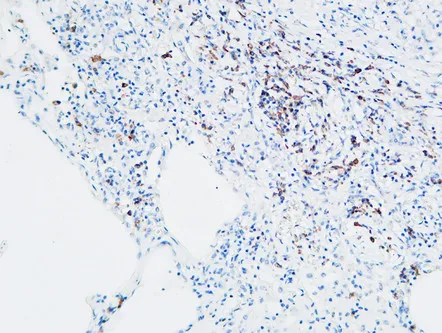

MPO Rabbit Polyclonal Antibody

Cat: APRab14056

Size1:50μl Price1:$118

Size2:100μl Price2:$220

Size3:500μl Price3:$980

Size2:100μl Price2:$220

Size3:500μl Price3:$980